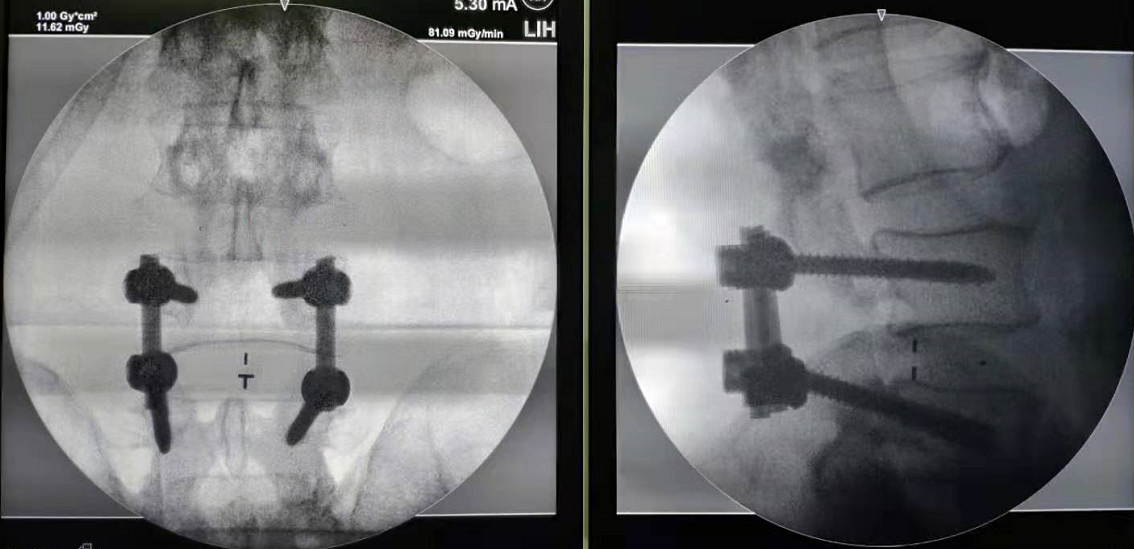

④经皮内镜下腰椎间盘切除术(PELD)

图片 14345 图片 14347

图片 14346